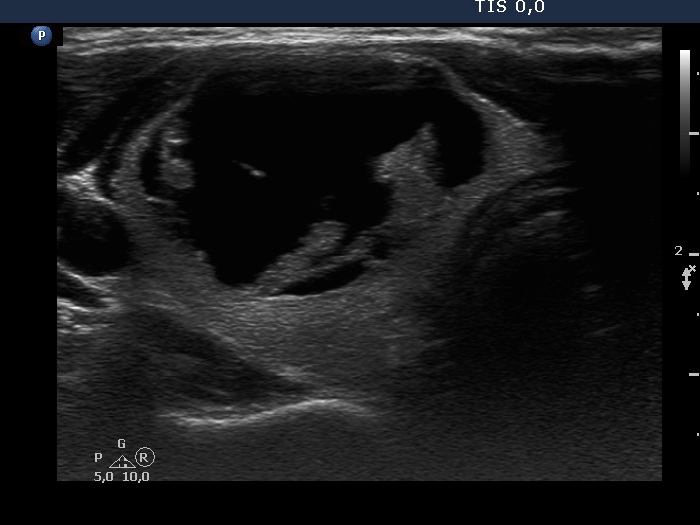

The composition of the nodule - case 753 (ultrasonographic picture 2)

Right lobe, another transverse scan. The solid part of the nodule is echonormal and has non-specific granulations and back wall figures caused by posterior enhancement. This is probably a peripheral-type cyst.